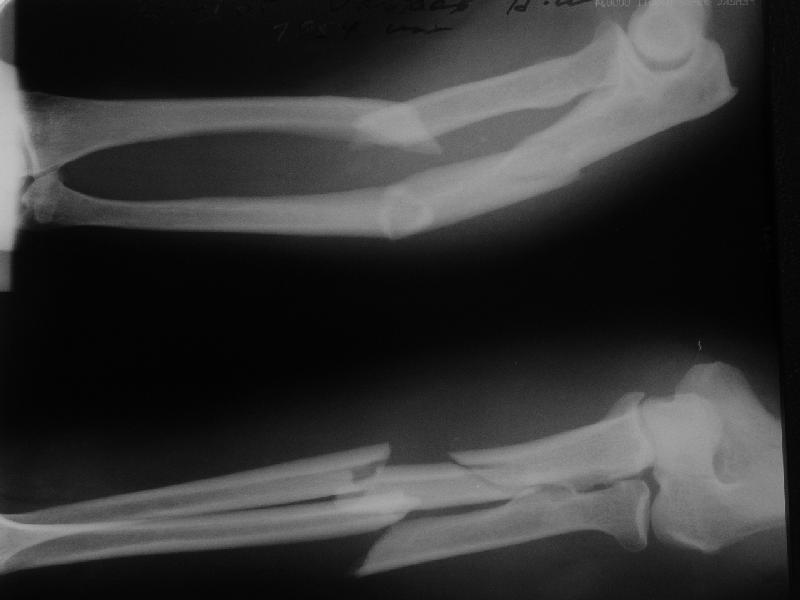

В приложении заключительный момент операции и итоговые снимки. Сделали закрыто. Оба гвоздя (ChM) заперты динамически не только из-за лени ;-) но и

потому, что форма линий излома такова, что и упор будет, и ротационной подвижности на месте переломов не ожидается. Комментарии и критика приветствуются.

The reductions are nice, but I'd be concerned that the fracture of the radius will move with pronation & supination encouraging nonunion (since the nail is essentially fixed to the distal radial shaft and free to move with respect to the proximal radius.

The reduction is excellent but I am not sure that you have rotational stability of the proximal radial fragment (no proximal locking) this could rotate with pronation and supination. If you are planning to cast then ORIF with plates is superior because casting is not necessary. I would expect these fractures to heal with callus as opposed to primary bone healing seen with plated fixation. Is healing with callus in the forearm a problem? I am not sure I know. How do these rods and locking screws compare price wise with plate and screw fixation (more expensive I would expect)? How often is hardware removal required? What was your operative time? I think these are all factors to consider when comparing a new treatment method with an established one.

Long arm cast for 2 weeks then Active ROM would be my approach. Is the elbow OK ?? radial head looks a little posterior though???

Good technique, but in comminuted / segmental #s like this ,isn't it better to lock statically at both ends? I would be concerned about possible rotation.I dont have any experience with closed nailing of forearm though. Is he going to be in a cast for 6 weeks?

Length 200 and 240 mm, diameter 4 mm.

Yes, the radius. The set includes cannulated reamers 4 and 5 mm. Though finally our custom-made 5 mm hybrid of reamer and awl was used.

Axis, length, radial bowing and rotation are restored. Stability is relative as in any nailing, but enough for early function.